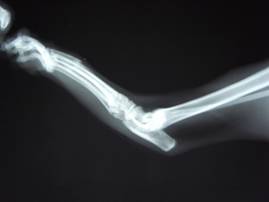

レントゲン検査にて、

右後肢第三中足骨が骨折していることがわかりました。

(右後ろ脚、中指にあたる部分の足の甲)

43-02